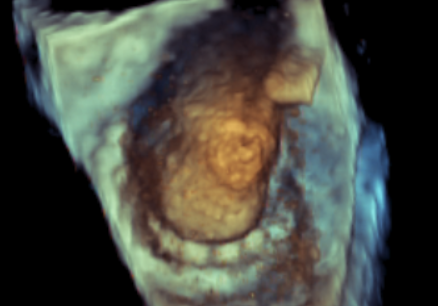

原生物瓣少量反流

过瓣流增快,呈“五彩状”

CDFI提示过瓣血流通畅

CDFI示少量瓣周漏